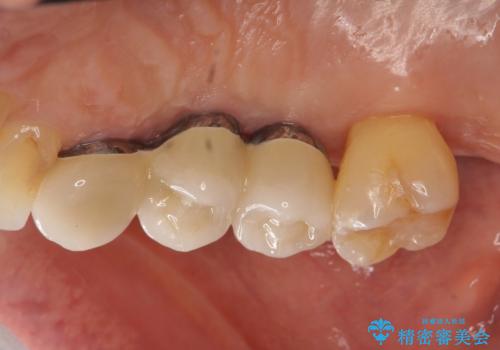

部分矯正を含む 歯周病治療 (再生治療・歯周ポケット除去・MTM・連結補綴)

連結補綴について

特定の歯に強く力がかかりまた歯周病により臨床歯根が短くなっているような場合、歯の動揺を抑えるため連結補綴が検討されます。

歯の動揺が続くとより周囲の骨を失い最終的には歯を喪失してしまう可能性が高くなってしまうためです。

今回連結補綴を行うにあたり、歯周病の問題を解決するために再生療法・歯周ポケット除去手術を、またより歯の神経を保存し力に対抗できる環境を整えるために小矯正を行い精度の高いメタルボンドクラウンを製作することができました。